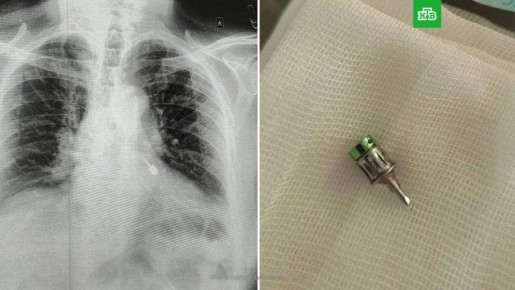

В средствах массовой информации сообщается, что во время лечения зубов в частной клинике в Мытищах в дыхательные пути пациента попал стоматологический бур. Мужчина своевременно обратился за помощью в другое медицинское учреждение, благодаря чему инородный предмет удалось извлечь.